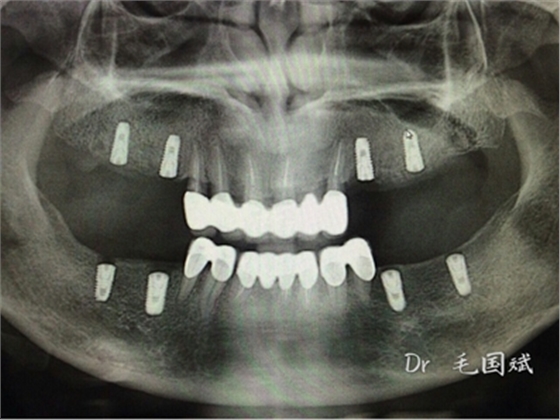

毛國(guó)斌種植病例——群討論分享